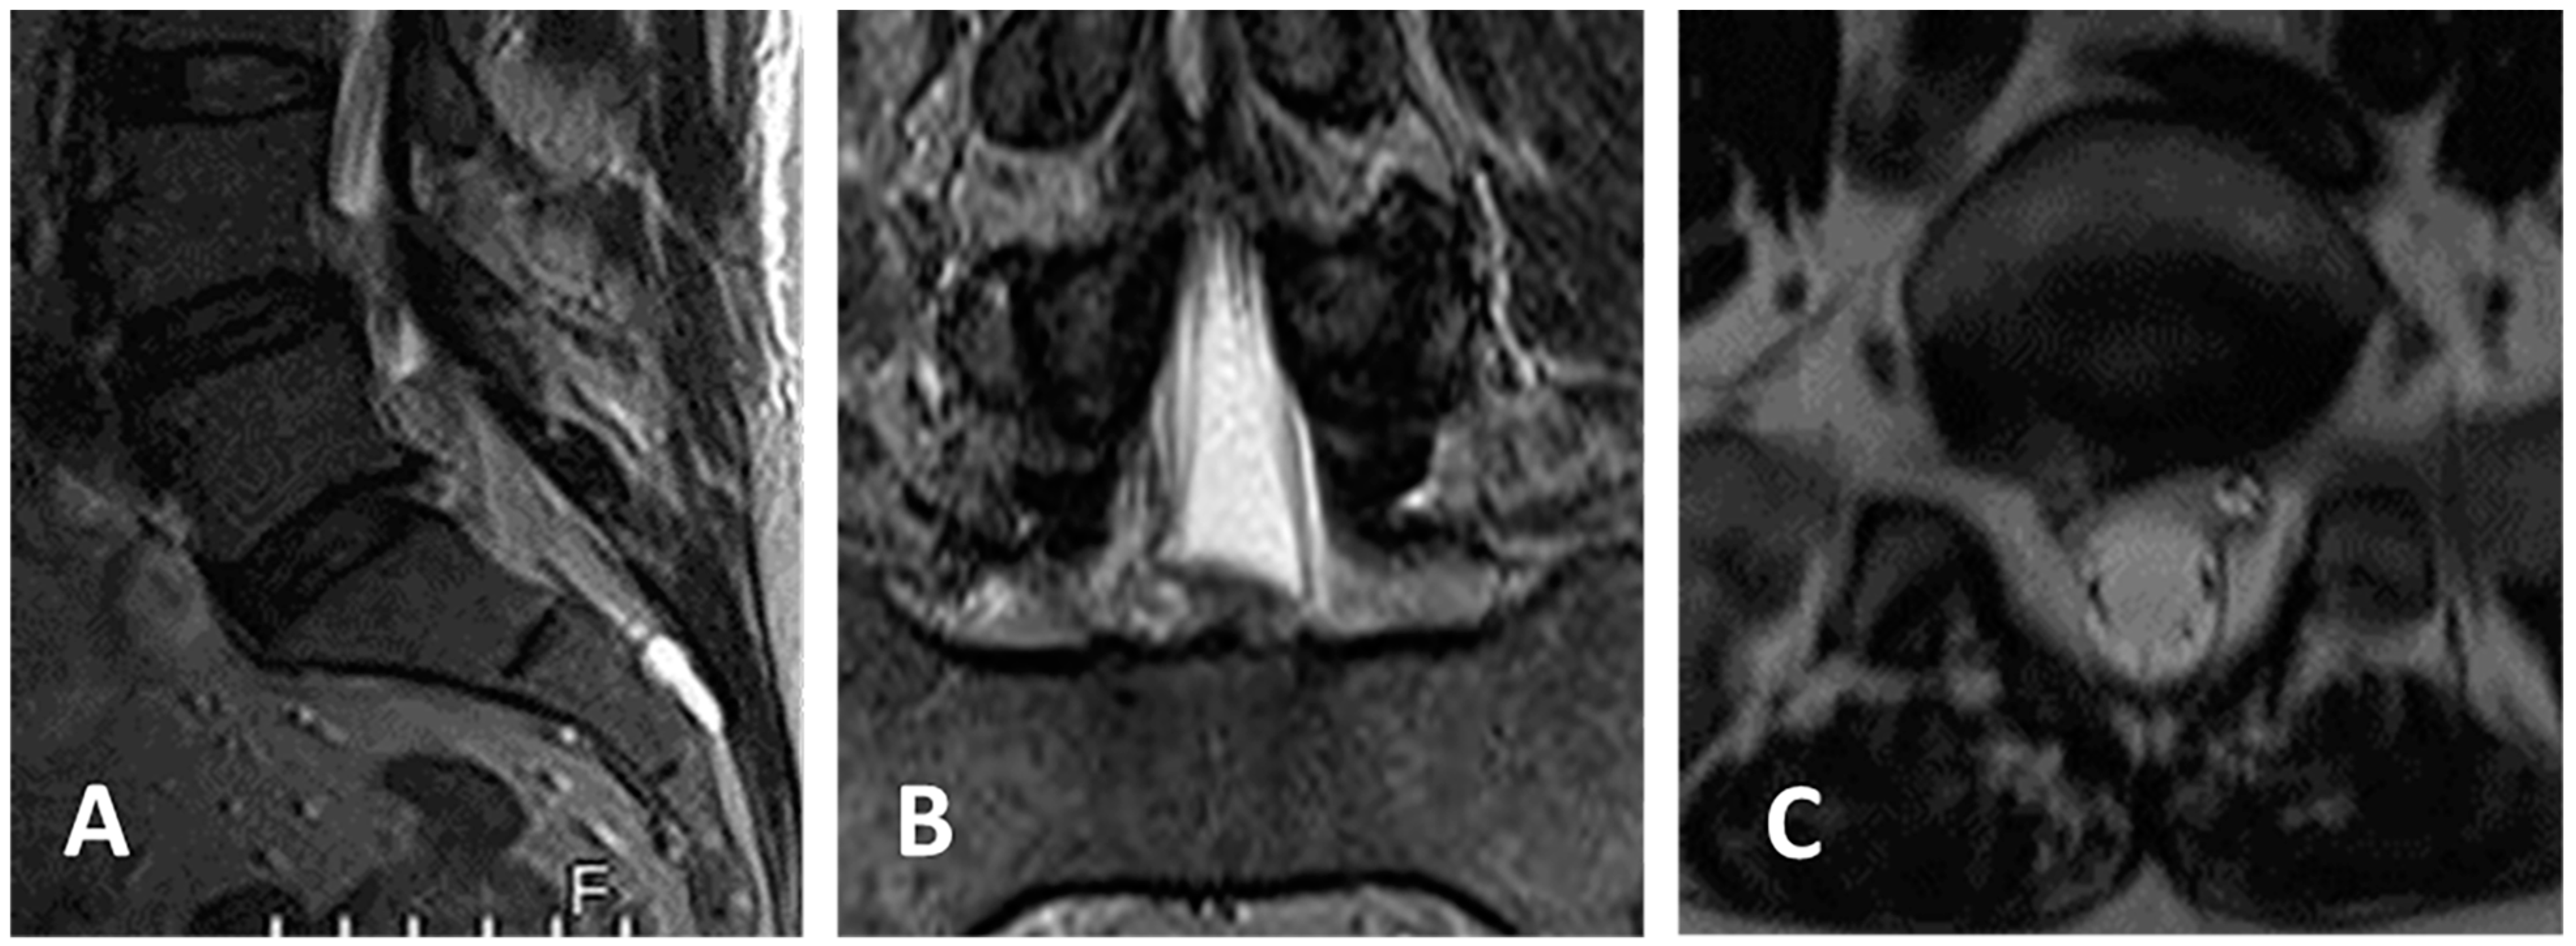

3.4. Clinical Case 2